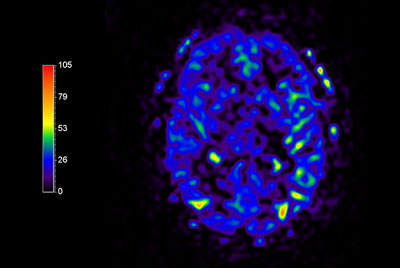

Multi Nuclei - Brain imaging (23Na)